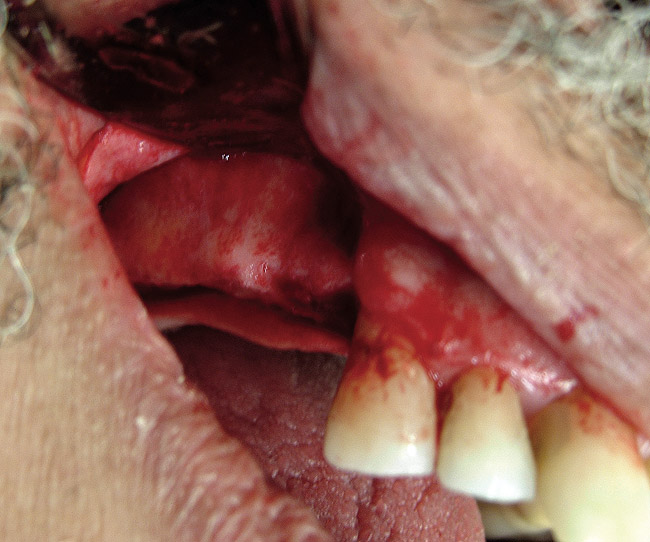

Figure  4  Placement of the graft.

Figure 4

Figure  7  The graft after suturing.

Figure 7